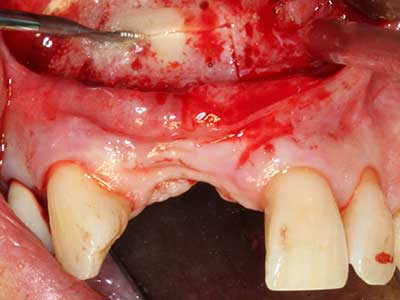

Piezo surgery has additional advantages when harvesting bone blocks. In addition to the high precision with osteotomy described above, the use of the thin saw tips specifically minimizes loss of material. Greater loss of material during harvesting can be expected with the thicker instrument tips, particularly when using Lindemann drills (Lakshmiganthan, Gokulanathan et al. 2012). The basal separation, which is necessary particularly for retromolar block transplants, is simplified by specially designed rectangular saws, with the result that piezo surgery is viewed as a precise, simple and safe procedure for harvesting retromolar bone blocks (Happe 2007) (Fig. 1-12).

Indication: Bone splitting

Bone tissue is not simply a mineral structure but also contains a substantial proportion of collagen fibres. This means it not only has good compressive strength but also a degree of flexibility, which can be taken advantage of when performing bone augmentations. In the classical expansion procedure using bone splitting, the atrophied alveolar ridge is split longitudinally and carefully expanded after reaching an adequate osteotomy depth (Fig. 13-16), ideally without substantial removal of the periosteum (Brugnami, Caiazzo et al. 2014, Stricker, Fleiner et al. 2014). Screw and plate systems with increasing expansion distance have proven effective in separating the two bone lamellae while remaining below the fracture threshold. In general, residual bone widths of at least 3–4 mm are required (Chiapasco, Zaniboni et al. 2006) to guarantee adequate flexibility and sufficient bone coverage of the future implants. If necessary, a vertical relief osteotomy on one or both sides can improve flexibility. A combination with additional augmentation techniques, particularly on the buccal side, has been described as an alternative to the classical technique.

The splitting procedure is particularly atraumatic and there is no significant loss of dimension when using piezosaws, and there are no significant differences between implants in split jaws and implants in an alveolar ridge without a bone deficit (Chiapasco, Zaniboni et al. 2006, Danza, Guidi et al. 2009). However, sufficient continuous irrigation is essential, particularly with locally restricted and deep splitting to prevent thermal stress in the apical osteotomy regions.